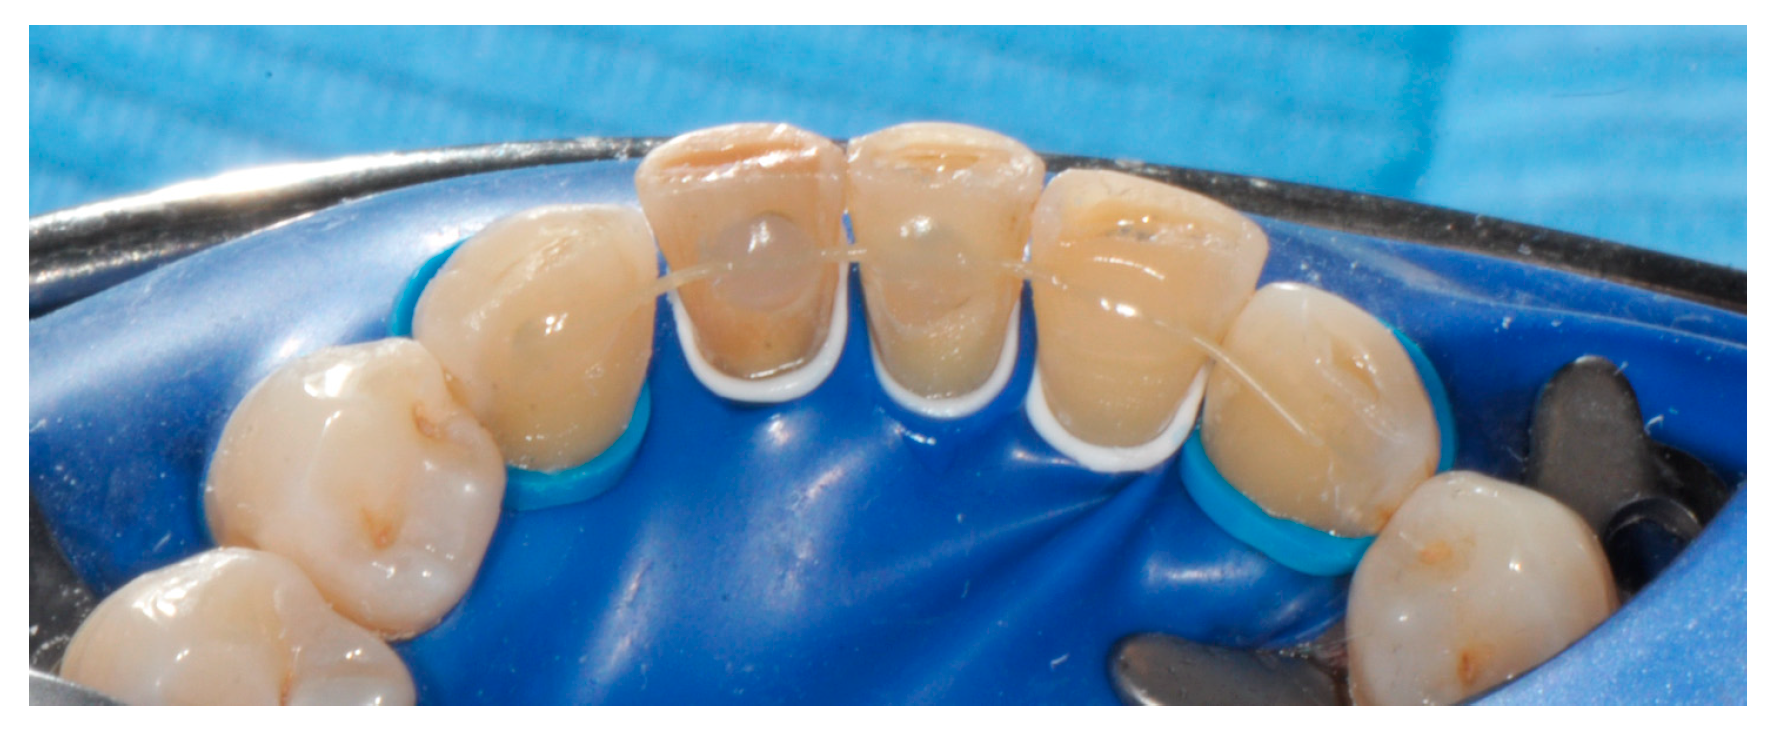

2. Materials and Methods